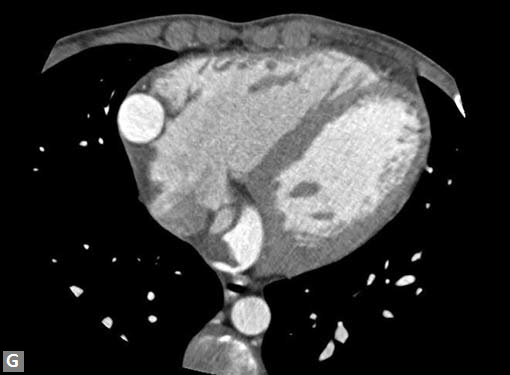

Connective tissue disease, hypertension and iatrogenic (Figs 19K to L) injury are the common causes for dissection. Radiologist not only establishes the diagnosis, also evaluates the extent of dissection, presence of thrombosis particularly in false lumen. In case of type A dissection, involvement of aortic root is determined. Relation of thrombosed lumen and ostia of coronary vessels, cephalad branches (Figs 19N, R to V) of aorta is determined. Most of the occasions membrane is demonstrated. Spiral nature of the membrane can be seen

Pericardial effusion may accompany type A dissection.

Hemopericardium is the dreaded complication of leaking

type A dissection (Figs 19S to V). The type B dissection can

Figs 19A to Y (A to C) Scannogram (A), plain (B) and contrast study (C) show partial anomalous pulmonary venous connection; (D to F) Heterotaxy; (G) Aortic occlusion; (H and I) Aortic stents; (J) Aortic dissection with ‘Benz’ sign due to second dissection within the true lumen; (K, L and M) Aortic dissection with thrombus in pseudolumen following catheter angiogram; (N) Aortic dissection involving common carotid arteries and subclavian artery; (O, P, Q and R) Aortic dissection with right renal artery arising from true lumen and left renal artery from false lumen; (S, T, U and V) Stanford B dissection with extension Y to iliac vessels; (W to Y) Aneurysmal dilation of ascending aorta